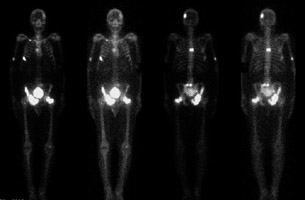

- Click on the image for a larger versionFBone scan. This shows numerous areas of increased tracer uptake. The left femoral fracture is seen as are metastases in the pelvis seen on the original pelvis radiograph. Spine, rib, and skull metastases are present.